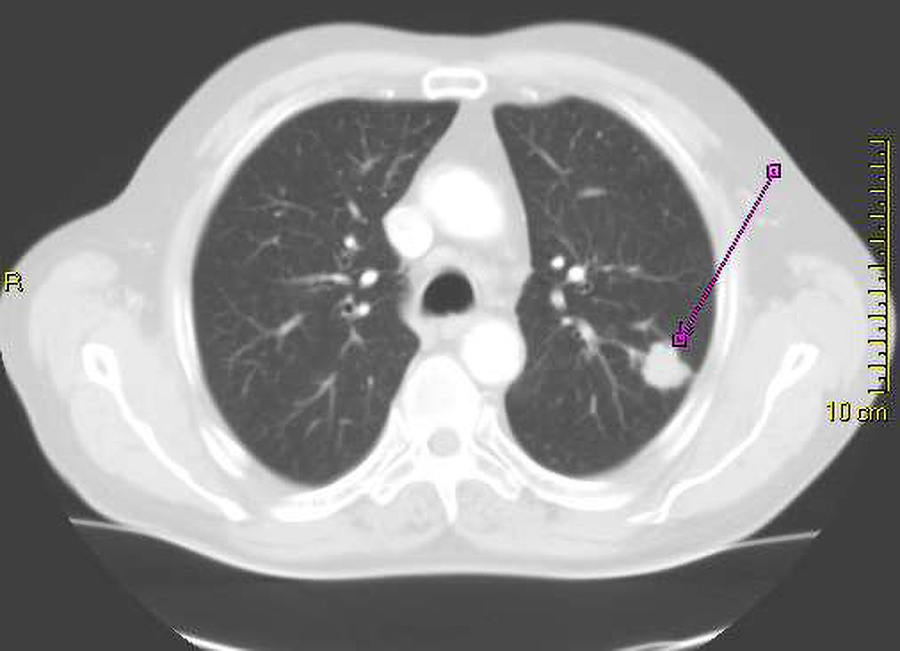

The image below is a chest CT that shows the lungs. Note that the image is a cross section, with the lungs to the left and right of the center. The bright white structure indicated by a purple line is a lung cancer. Note that most of the lungs are gray with some white spots and lines.

A chest CT shows the lungs.